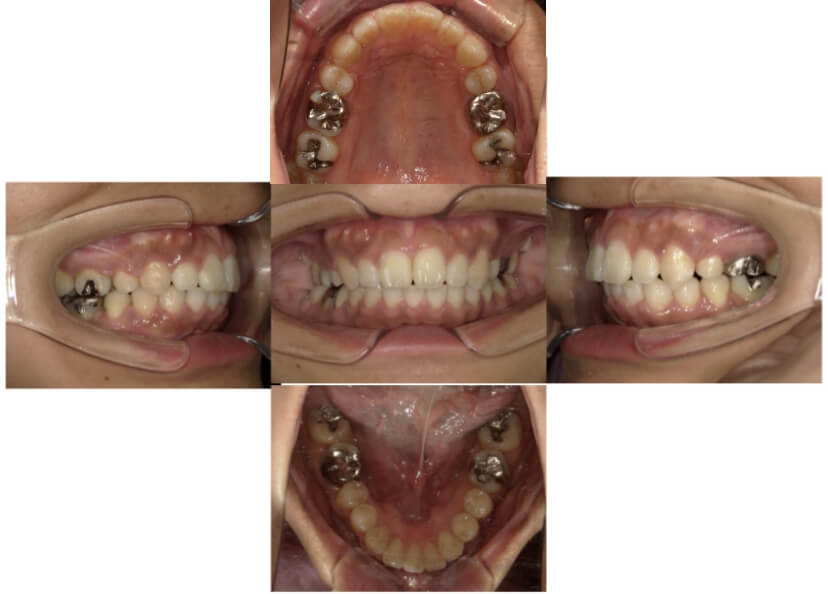

症例1

上顎前突、叢生

抜歯

ブラケット矯正

上下顎叢生、上顎前突(出っ歯、上下の前歯のガタガタ)のケースです。

装置はラビアル(上下表側)で、上顎の小臼歯を2本抜歯を行っています。抜歯したスペースを使って、上の前歯の後方移動と叢生(ガタガタ)と出っ歯の改善を行っています。下は歯と歯の間にIPR(隣接面削合)を行い、スペースを確保し、叢生の改善を行っています。

主訴 前歯のガタガタと出っ歯が気になる。

年齢・性別 47歳 女性

お住まいの地域 神奈川県川崎市

治療方針 抜歯スペースおよびIPRを利用して上前歯の叢生(ガタガタ)の改善

抜歯部位 上顎左右第一小臼歯

使用装置 ラビアル(上下表側)、顎間ゴム

治療期間 2年0か月

治療回数 15回

リテーナー クリアリテーナー

BEFORE

AFTER